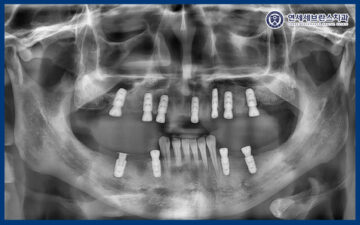

26.01.12

치료 마무리 후 파노라마 사진을

찍어보았을 때도

임플란트가 계획한 위치에

안정적으로 식립된 모습을 확인할 수 있었으며,

전체적인 배열과 교합 균형 역시

양호한 상태로 유지되고 있었습니다.